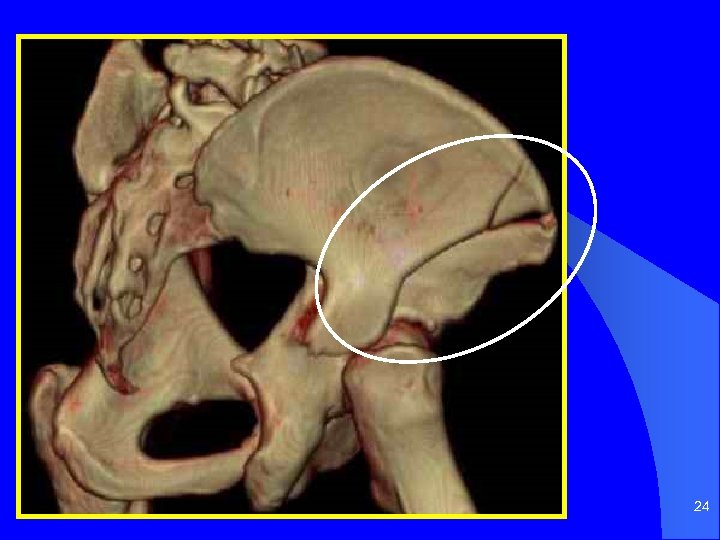

23

24